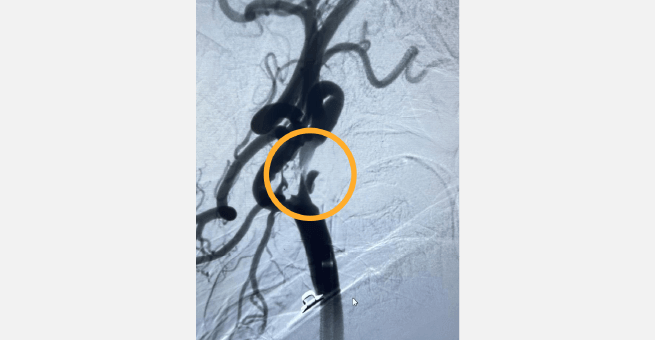

একজন 60 বছর বয়সী মহিলা 3/5 শক্তি সহ বাম উপরের এবং নীচের অঙ্গগুলির দুর্বলতার অভিযোগ নিয়ে হাজির। ইমেজিং অভ্যন্তরীণ ক্যারোটিড ধমনীতে 80-90% স্টেনোসিস সৃষ্টি করে একটি আলসারযুক্ত এথেরোম্যাটাস প্লেক প্রকাশ করে। সময়ের সাথে সাথে, রোগীর দুর্বলতা 0/5-এ বেড়ে যায়, অ্যাফেসিয়া সহ, সম্ভবত হাইপোপারফিউশনের কারণে।

ডিএসএ এবং এমআরআই স্ক্যানগুলি অভ্যন্তরীণ ক্যারোটিড ধমনীতে উল্লেখযোগ্য স্টেনোসিস সৃষ্টি করে আলসারযুক্ত অ্যাথেরোমেটাস প্লেকের উপস্থিতি নিশ্চিত করেছে।